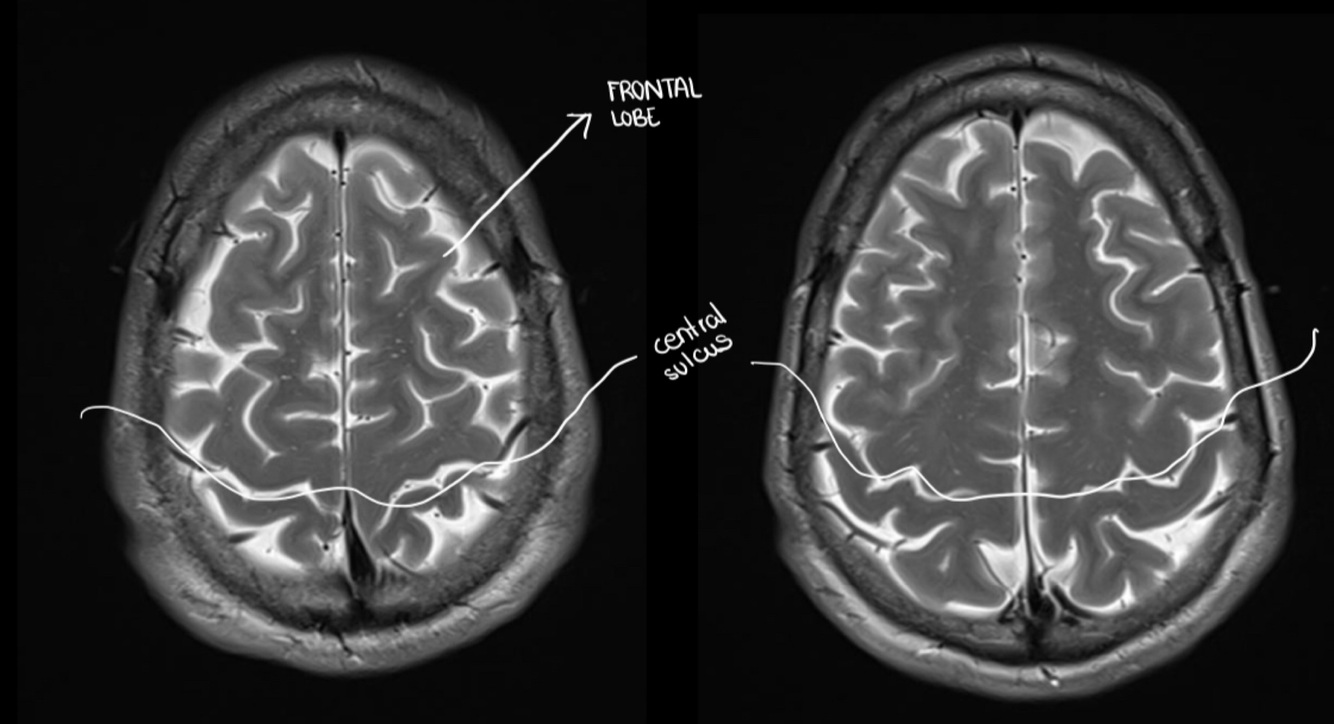

A lesion in this area might cause, problems in the contralateral… (hand/leg)

HAND (more lateral)